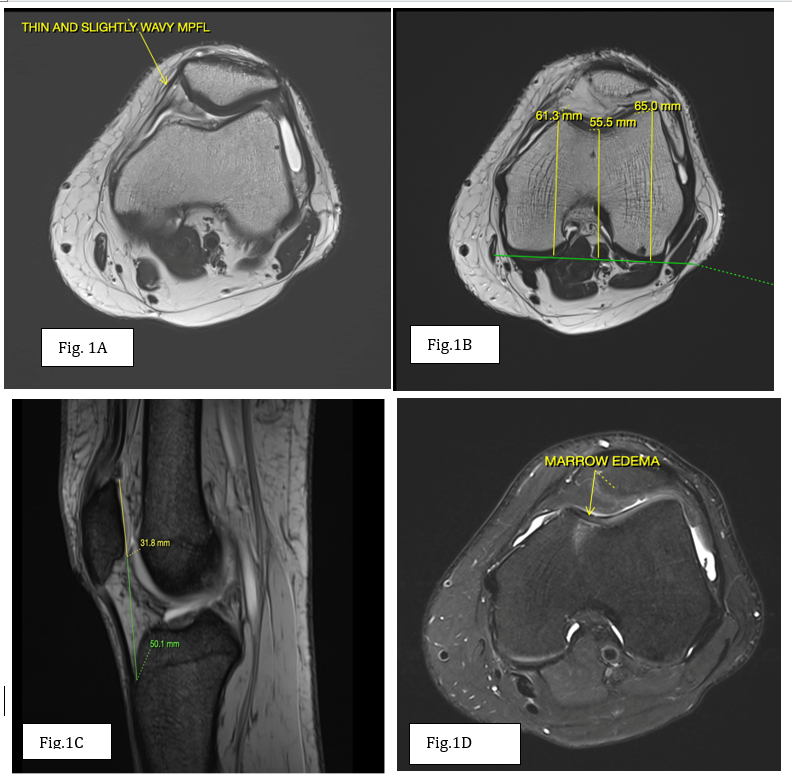

A 24-year-old male presented with recurrent episodes of the right patellar dislocation. There was no history of trauma, prior knee surgery, or congenital abnormalities. On physical examination, a positive patellar apprehension sign was noted. MRI of the right knee revealed mild lateral subluxation of the patella. The MPFL appeared attenuated and wavy but remained intact, without evidence of edema or tear. The tibial tuberosity-trochlear groove (TT-TG) distance was within normal limits, and no features of trochlear dysplasia or patella alta were identified. Subchondral marrow edema was noted in the medial femoral condyle. In addition, a small cartilage defect with associated marrow edema was seen in the medial patellar facet, consistent with early chondromalacia (Fig 1). These findings suggest that repetitive microtrauma due to MPFL laxity is contributing to the patient’s recurrent instability and early cartilage degeneration.

Figure 1 : (a) Axial T2 weighted image showing thinned and lax medial patello-femoral ligament. (b) Axial T2 weighted image showing normal trochlear depth i.e., >3 mm. (c) Sagittal T2 gradient echo sequence showing normal modified Insall-Salvati ratio<2 (d) Axial proton density fat suppressed image showing small cartilage defect with associated edema in medial patellar facet consistent with early chondromalacia-likely secondary to repetitive microtrauma.